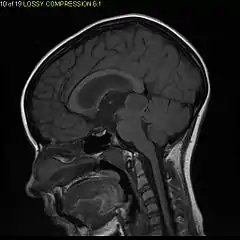

Usually – depending on the interview of the patient and after a clinical exam which includes a neurological exam and an ophthalmological exam – a CT scan and/or an MRI scan will be performed to confirm the presence of a tumor. They are usually easily distinguishable from normal brain structures using these imaging techniques. A special dye may be injected into a vein before these scans to provide contrast and make tumors easier to identify. Pilocytic astrocytomas are typically clearly visible on such scans, but it is often difficult to say based on imaging alone what type of tumor is present.